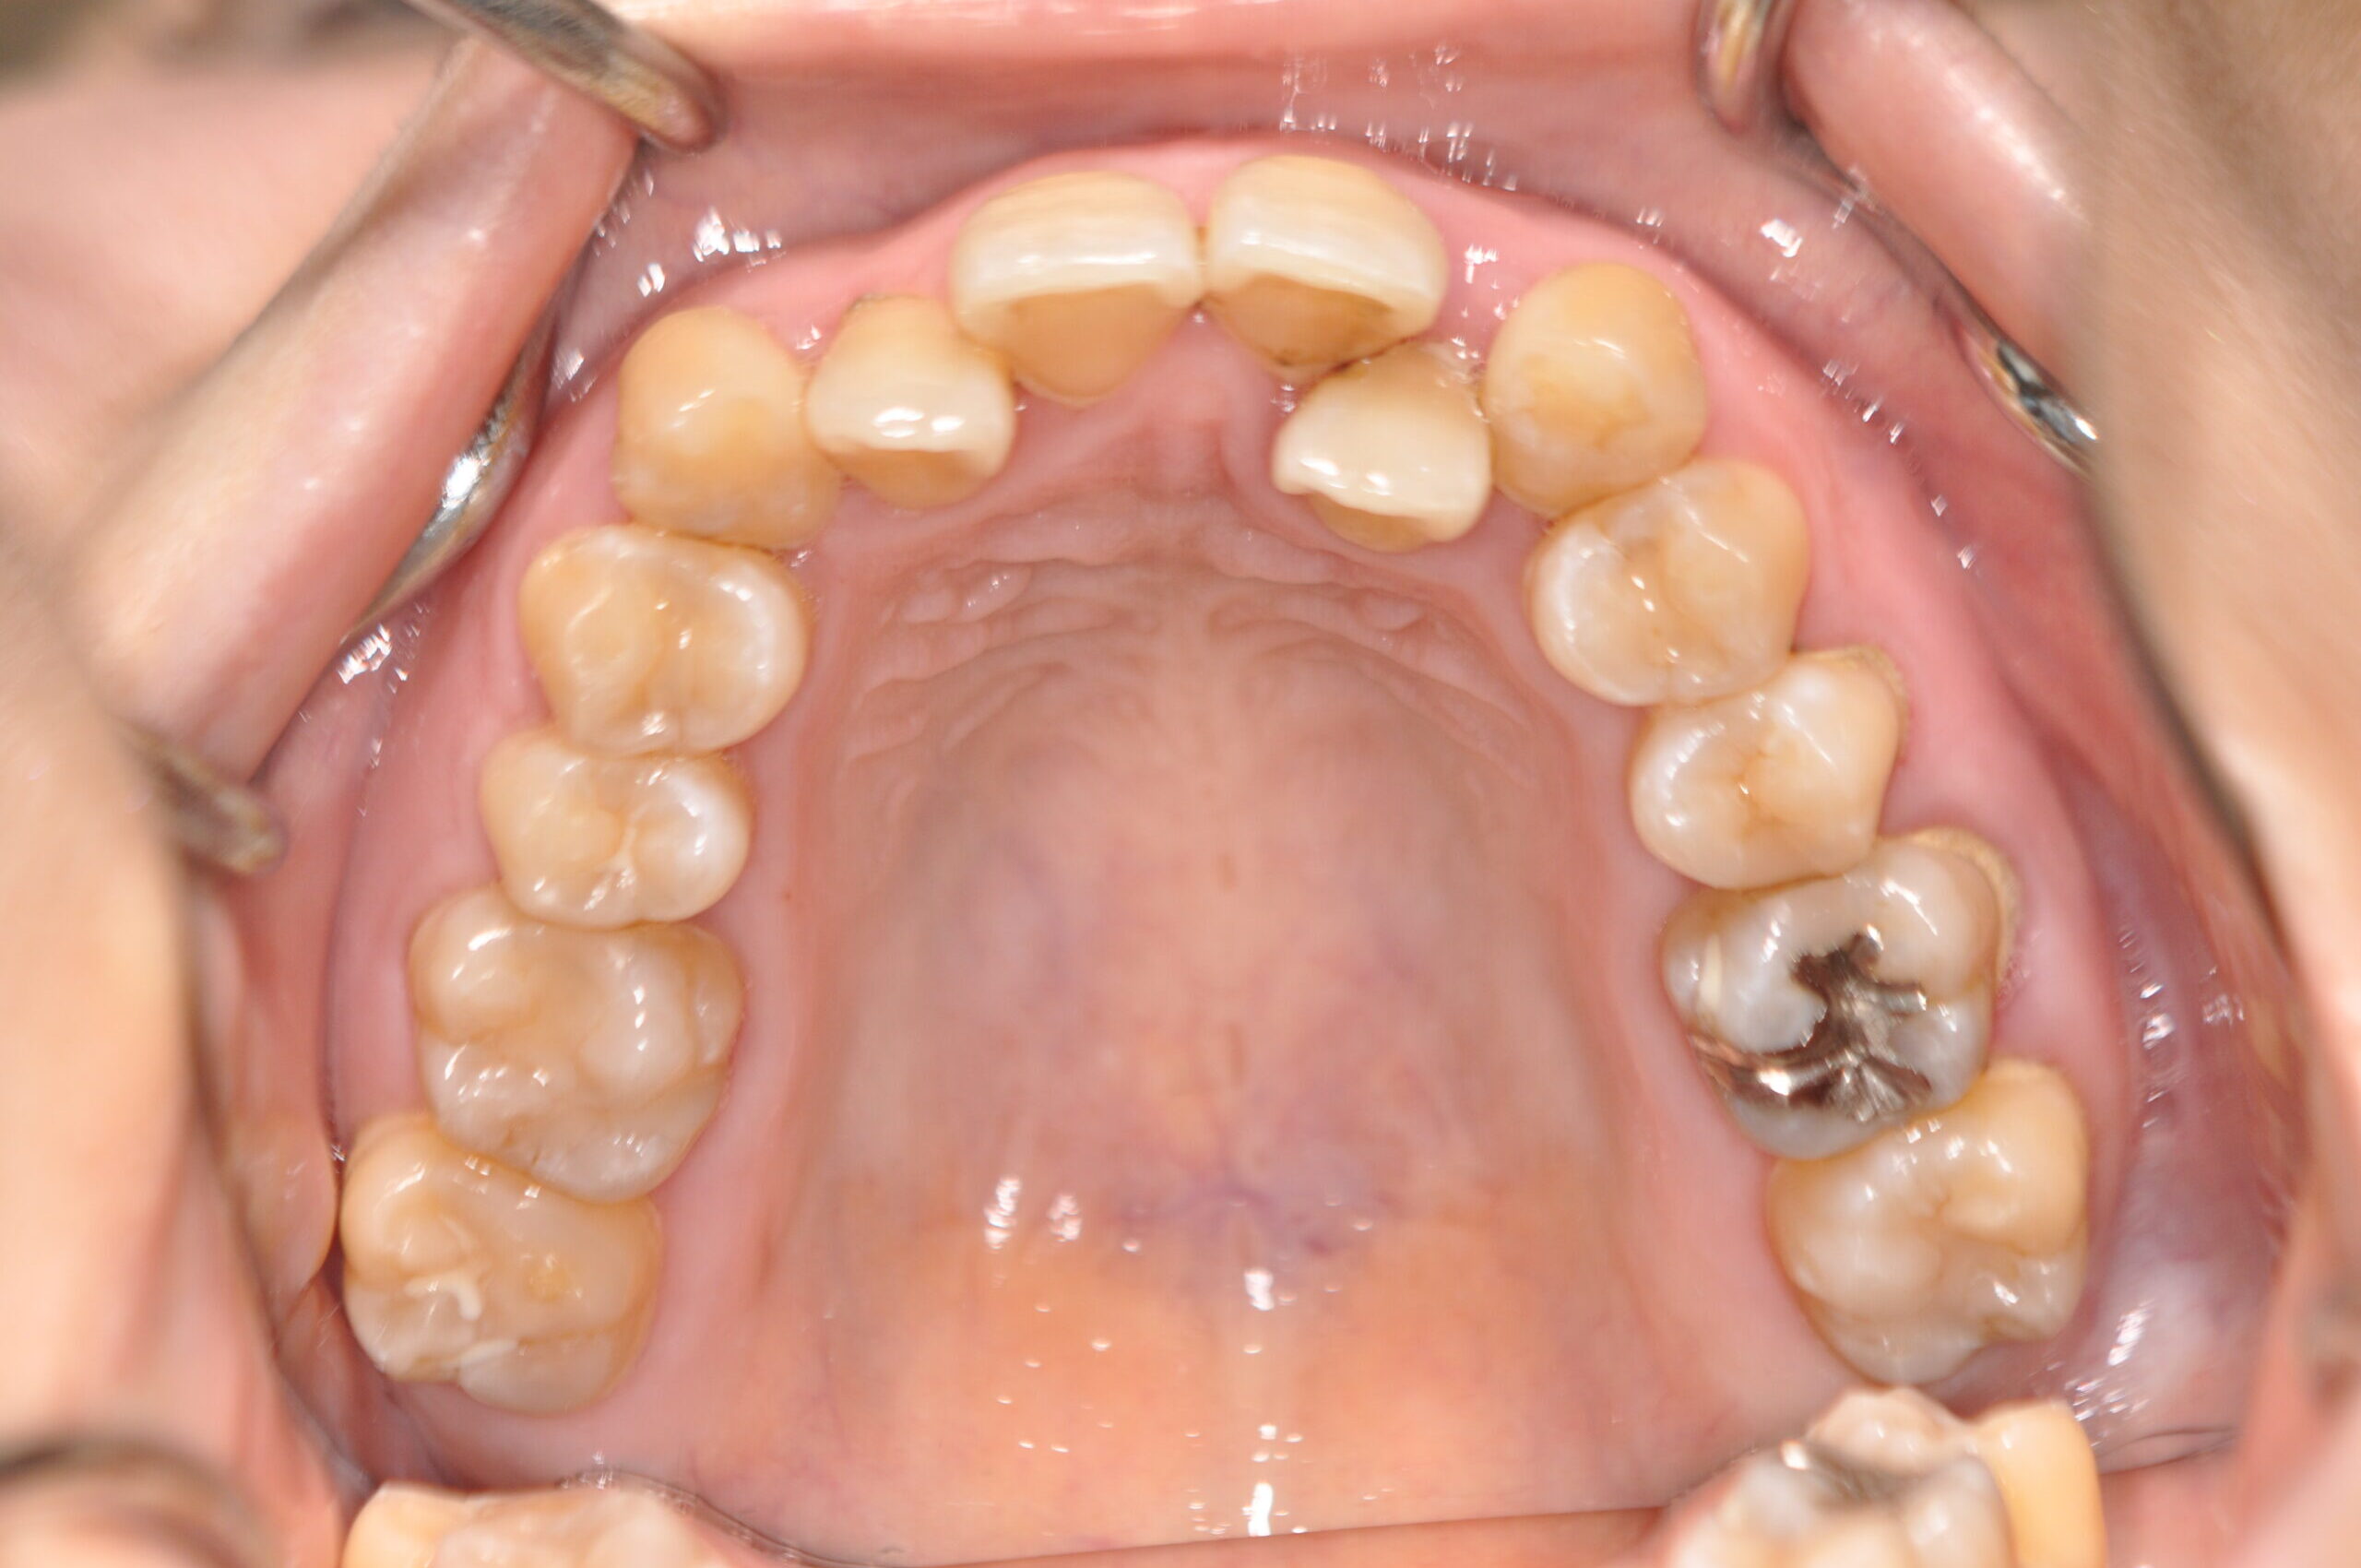

| 治療内容の詳細 | 初診時31歳の女性で、前歯が奥側にあることを気にされ来院されました。 検査の結果、上下顎叢生を伴うアングルⅠ級不正咬合と診断しました。 治療としては、上顎臼歯部の遠心移動を行い、歯を配列するためのスペースを確保し、非抜歯の上、セルフライゲーションブラケット装置(デーモンシステム)で歯の配列と咬合関係の改善をを行いました。 治療期間は、2年7ヶ月でした。 |